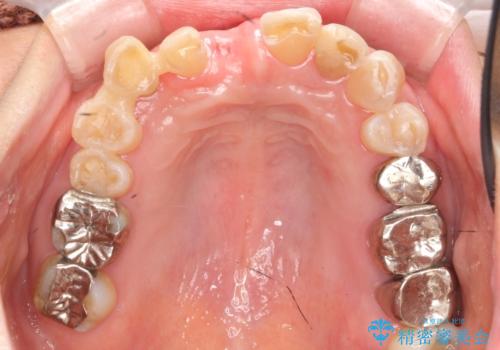

過度な咬合力 歯ぎしりで抜けた歯の欠損補綴

- 前歯を噛みしめにより失い、さらに犬歯もグラグラになり全く噛めなくなり改善を求めて来院されました。

過度な力がかかり周囲の骨に高度な吸収が見られた犬歯は抜歯し、機能・審美性の回復をより咬合力に対して抵抗力のあるブリッジ補綴にて対応します。